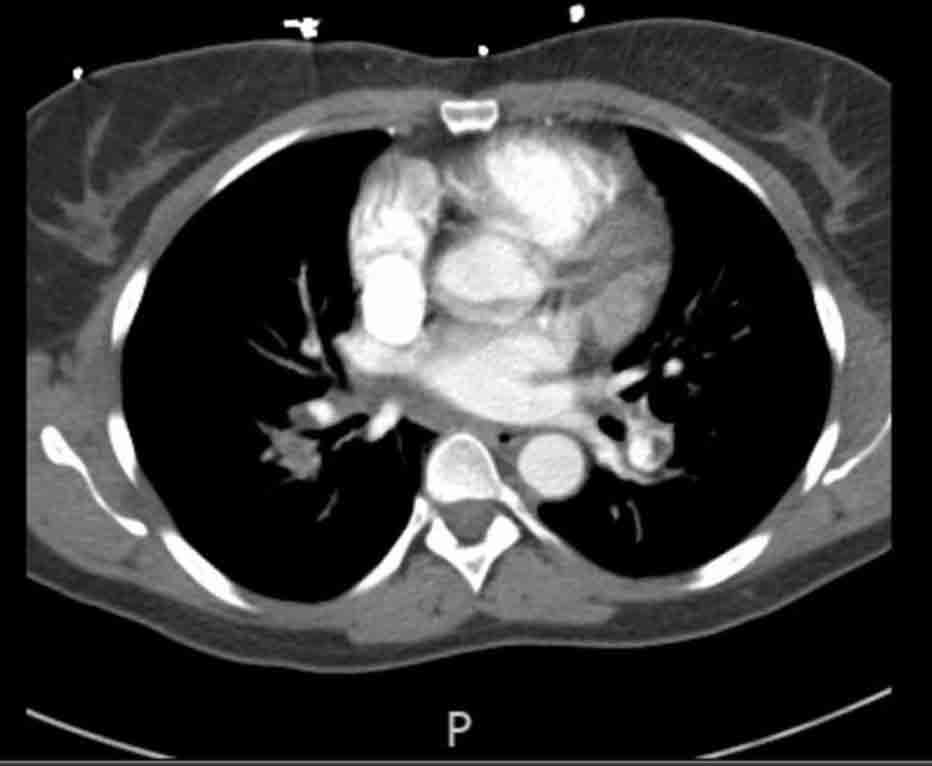

CT scan of the chest with IV contrast is obtained and shows a filling defect in bilateral upper and lower segmental pulmonary arteries on pulmonary arterial phase.